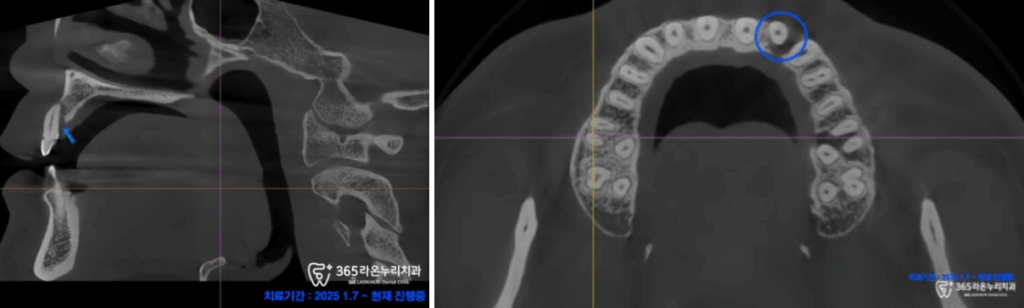

치근단 사진과 엑스레이 사진에서 확연하게

원심 치근의 골소실이 관찰되어,

정밀 진단을 위한 CT 촬영을

진행했습니다.

그러자 CT 사진에서 골소실

부위가 명확하게 나타나고 있었는데요.